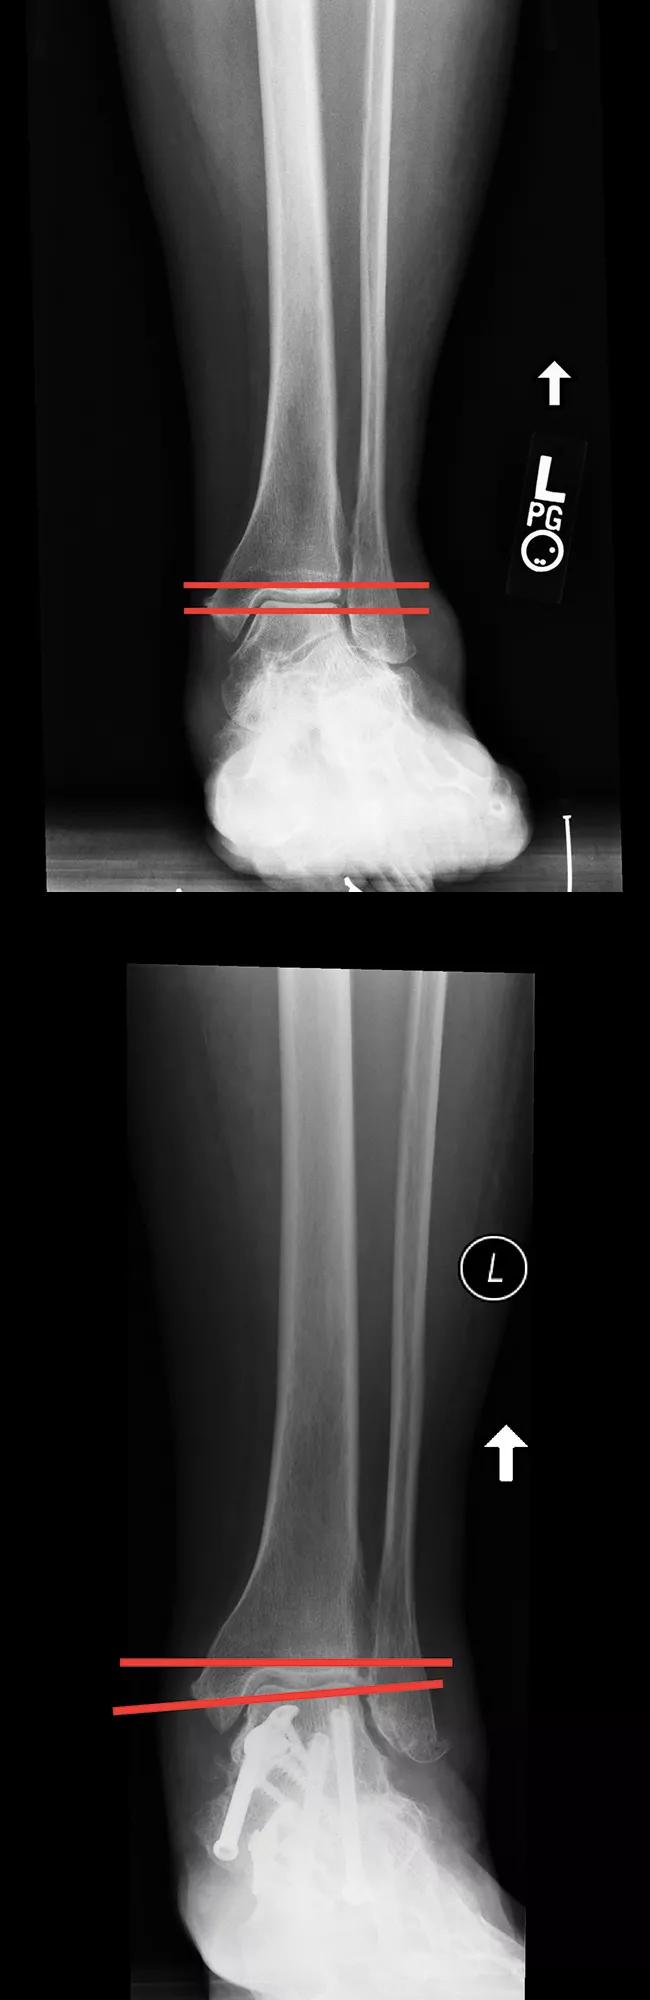

Figure 2. A. A large preoperative deformity. B. An undercorrected deformity.